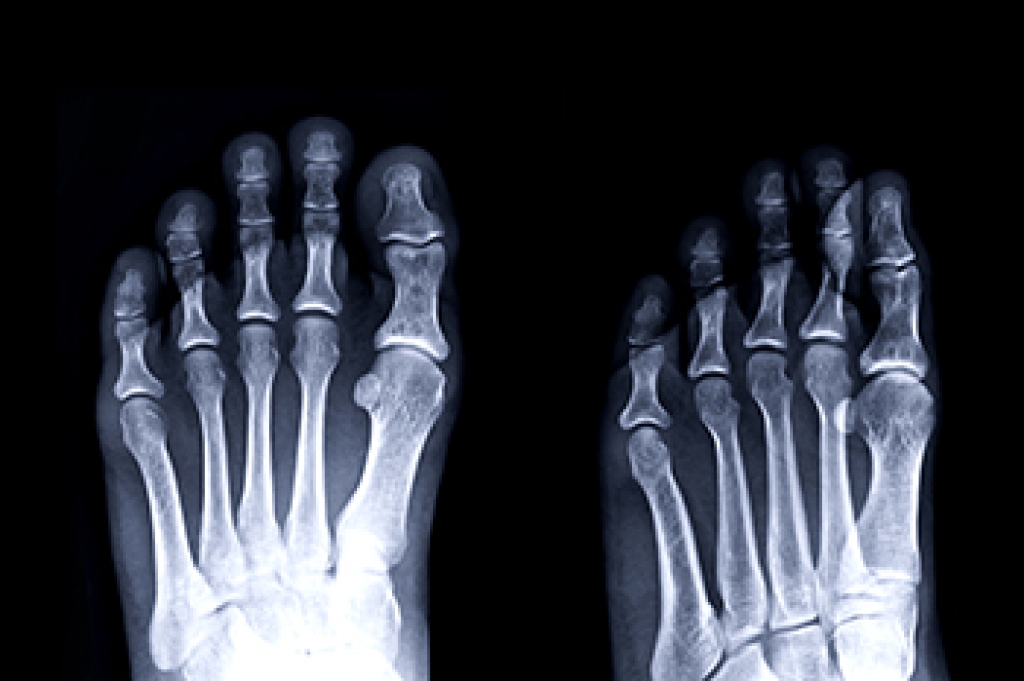

Podiatric biomechanics is a particular sector of specialty podiatry with licensed practitioners who are trained to diagnose and treat conditions affecting the foot, ankle and lower leg. Biomechanics deals with the forces that act against the body, causing an interference with the biological structures. It focuses on the movement of the ankle, the foot and the forces that interact with them.

Modern technological improvements are based on past theories and therapeutic processes that provide a better understanding of podiatric concepts for biomechanics. Computers can provide accurate information about the forces and patterns of the feet and lower legs.